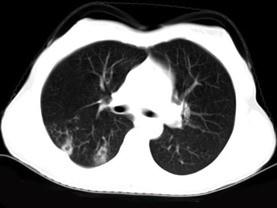

问题 女,40岁,间断咯血一周,低热,行胸部CT扫描如图,选择最可能的诊断为 ( )

选项 A、支气管囊肿并感染 B、肺脓肿 C、肺部感染 D、支气管扩张并感染 E、肺结核

答案 E